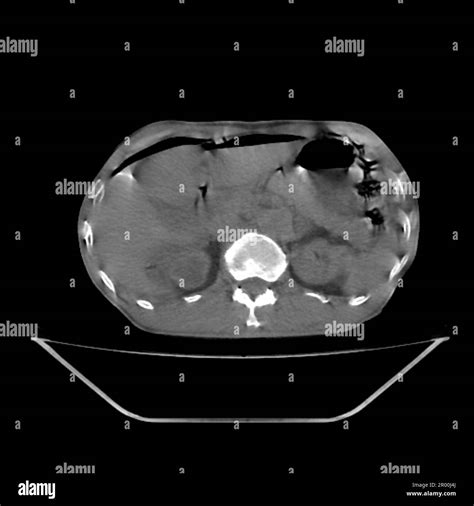

The radiation dose from a CT scan can vary significantly depending on the type of scan and the area of the body being imaged. The following table provides an approximate range of radiation doses for different types of CT scans:

Type of CT Scan Approximate Radiation Dose (mGy)

Head 1-2

Chest 7-8

Abdomen/Pelvis 10-20

Full Body 30-40

It’s important to note that the risk to the fetus depends not only on the radiation dose but also on the stage of pregnancy. The first trimester is the most critical period, as this is when organogenesis occurs. The risks decrease as the pregnancy progresses.